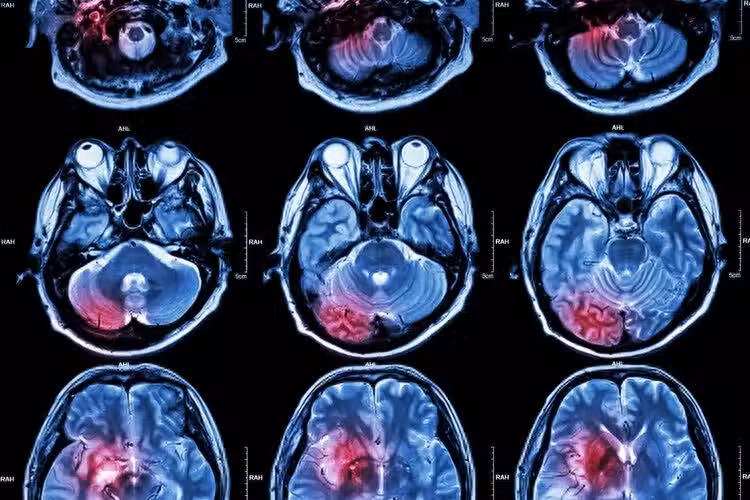

所謂腦出血,就是出血性腦卒中,是腦卒中(中風)的一種。發病率佔到全部腦卒中疾病的20%-30%,急性發作期的致死率高達30%到40%。腦出血好發於40-65歲年齡段,並且發病率會隨著年齡增加而提升。

大部分的腦出血是由於大腦內硬化的小血管破裂而致。長期的高血壓讓血管壁變得十分薄脆,血壓一旦突然升高,血管就會破裂,導致腦出血。因此,腦出血又被稱為「高血壓性腦出血」。